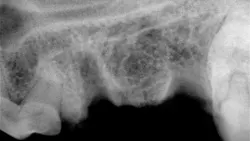

Preoperative radiograph of the maxillary left 4th premolar

Step 1

The site is radiographed postoperatively (A) and the mucoperiosteal flap is closed using absorbable suture in a simple interrupted pattern (B).